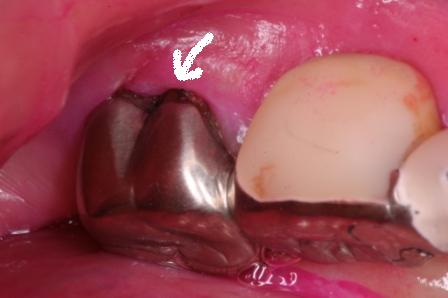

下顎7番の頬側歯茎部カリエスの原因 2025.06.04